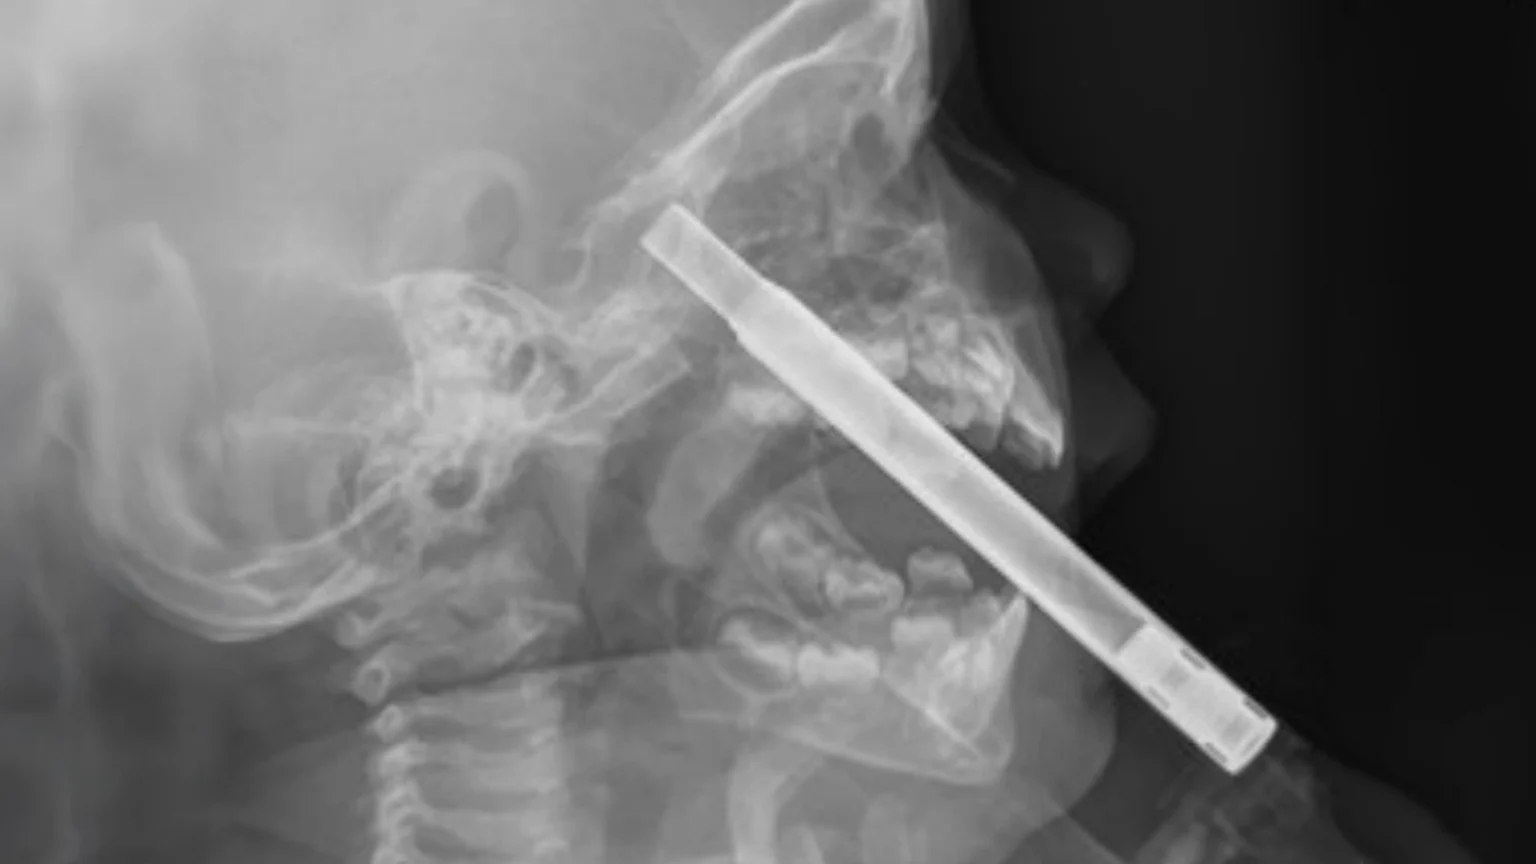

The X-ray showed the straw had pushed up into her nasal sinuses, “with the tip possibly sitting at the frontal skull base”.

Photo | New Zealand Medical Journal

A follow-up CT scan confirmed one end of the straw was lodged in the toddler's sphenoid bone, which sits right at the base of the cranium.